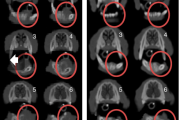

Suu limaskesta haavandid

- Alati tuleb kontrollida hambaproteese. – Haavandi põhjuseks võib olla odontoloogiline infektsioon. – Igal juhul tuleb arvestada vähi võimalusega. Reeglina tuleb võtta biopsia haavanditest, mis kahe nädala jooksul ei parane. – Konsulteerida hambaarstiga; patsiendid, kellele tuleb teha Loe edasi »